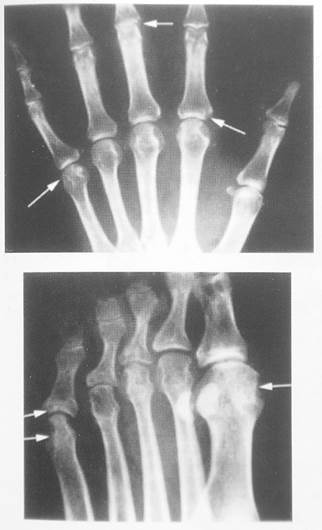

Рентгенография суставов – см. рисунок.